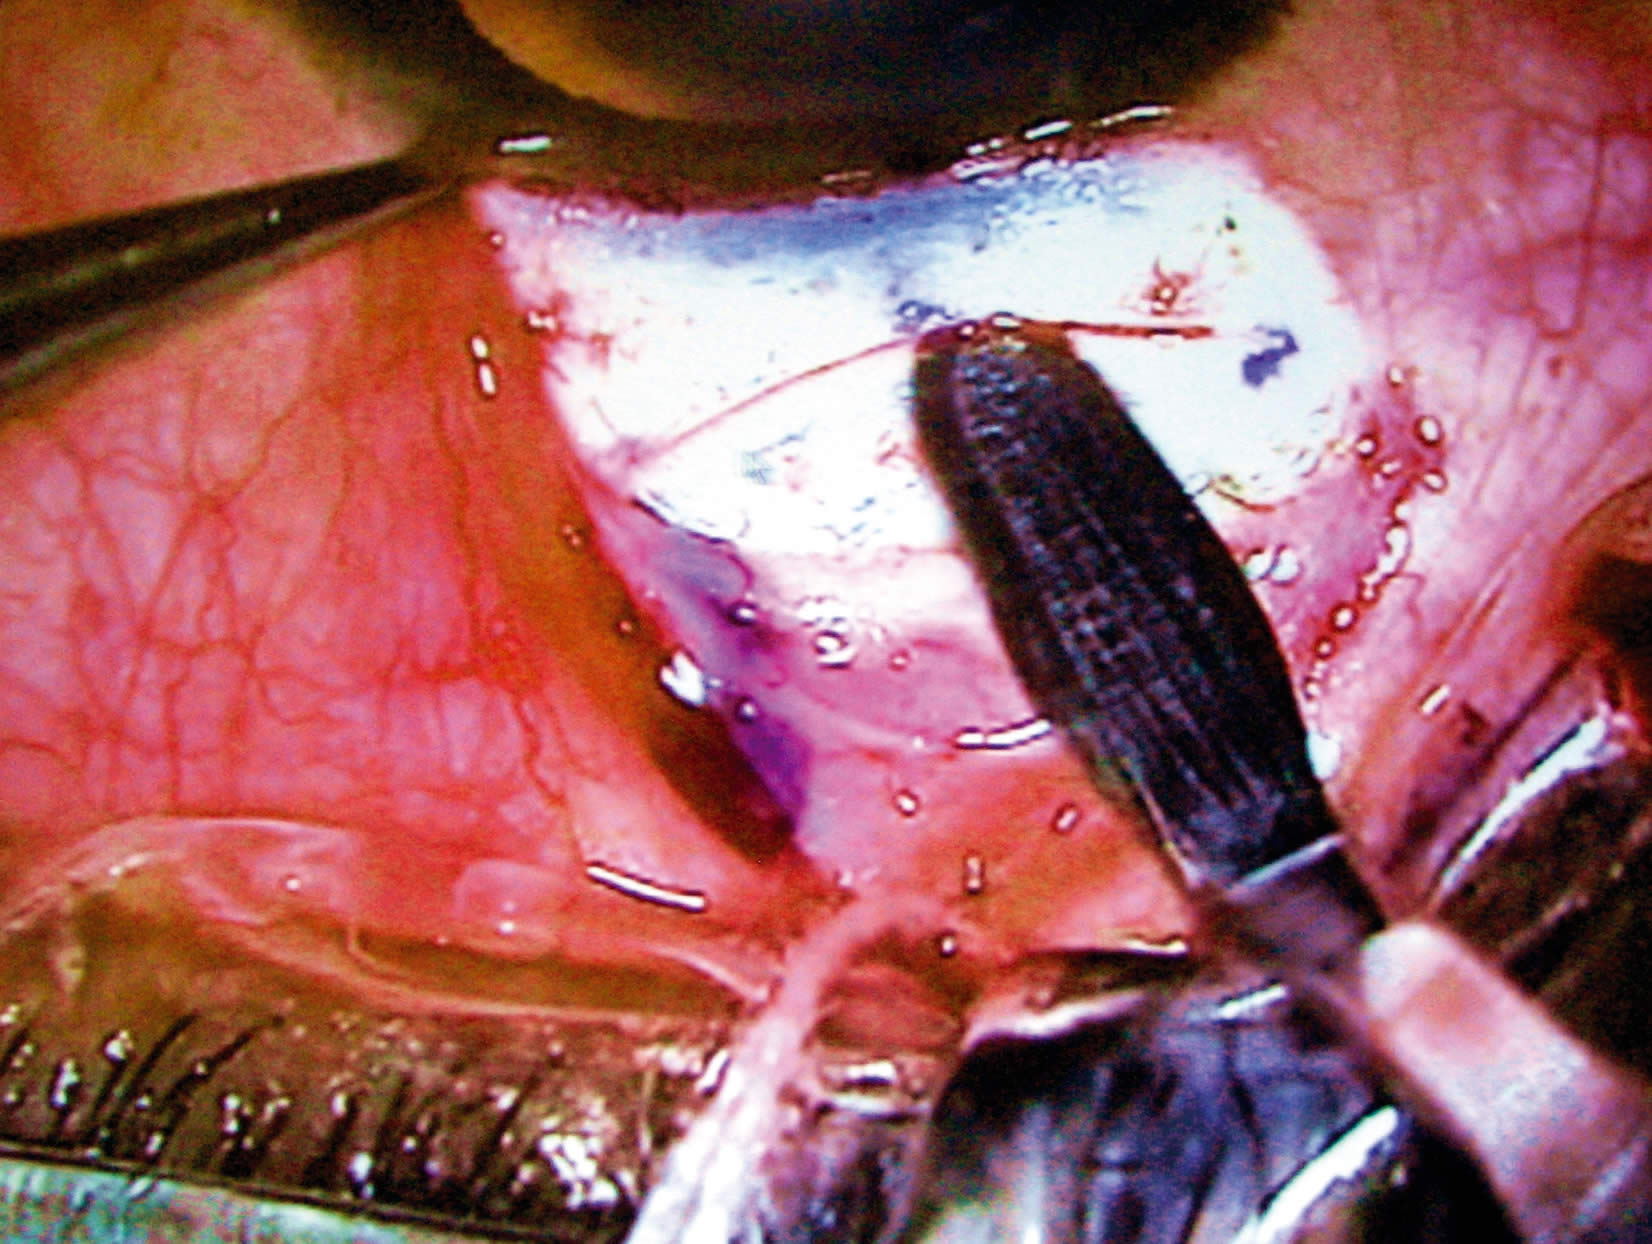

- fracture of the nucleus using an Akahoshi pre-chopper (Figure 1).

Chiriboga stressed the importance of using two different pre-choppers: a sharp one for harder nuclei and one with a wider point for softer cataracts.